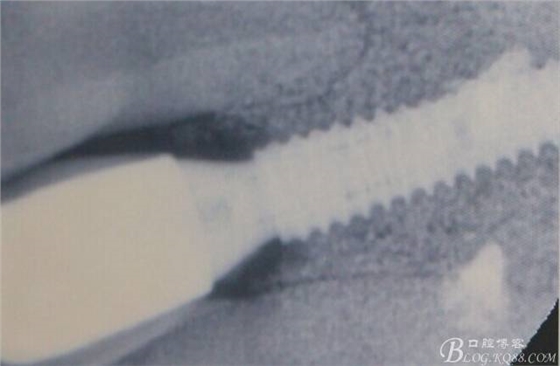

術(shù)后X光片。

術(shù)后1個月。

術(shù)后5個月。

骨高度穩(wěn)定。